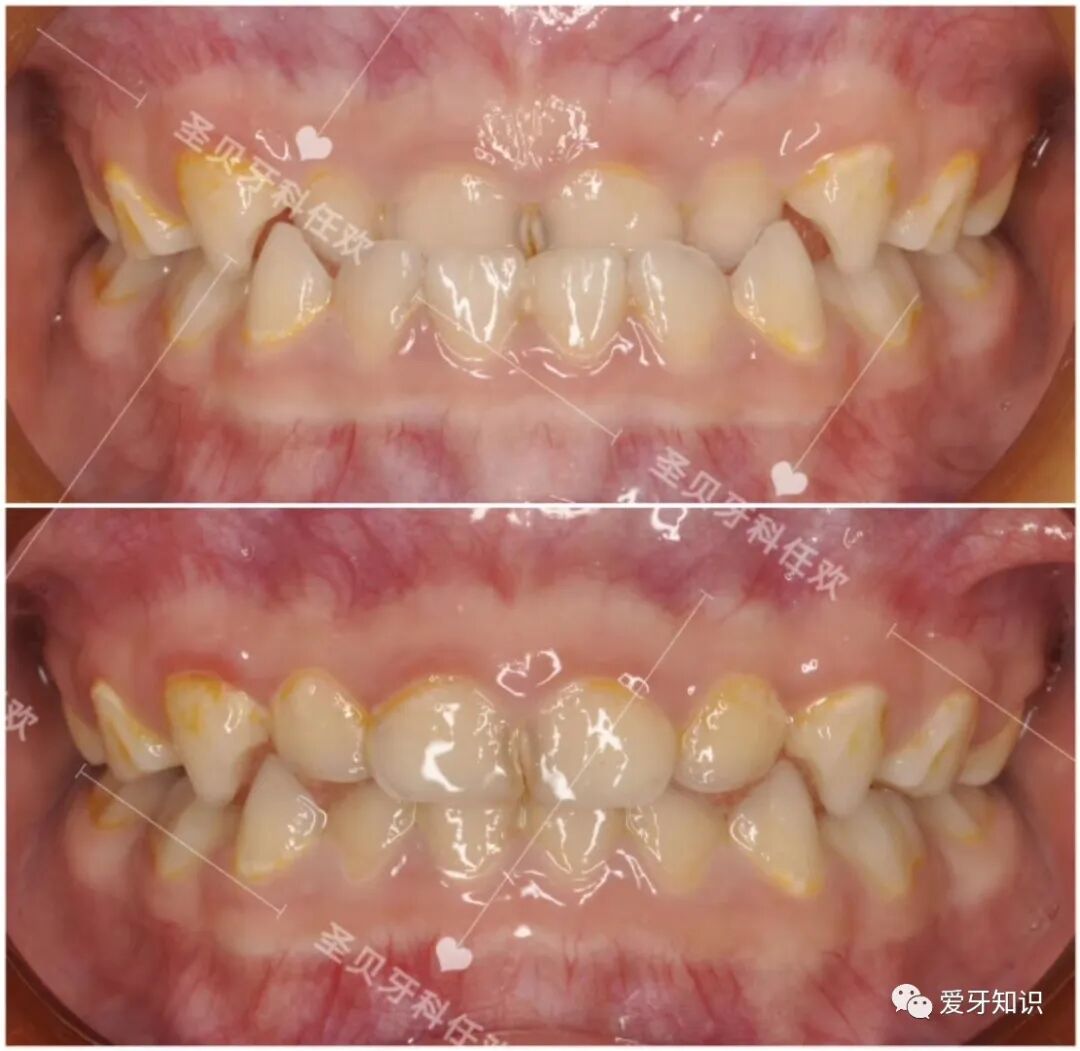

像这样的龅牙+嘴凸矫正变化就很大。于是拔掉了4颗正畸牙然后内收牵引,达到嘴型变化的过程!https://mmbiz.qpic.cn/mmbiz_png/fwaTu5a4jNI7P9JsNol5Bntcf4QDLzTxjUPJxibamWl8FlvEjBXATic1e69qaO5R2qEFh1OB2ddeaiam3YD4biaZAQ/640?wx_fmt=png

下面来自张敏同学的矫正体验和心得感言:

大家好,我是张敏,第一个需要做二次矫正的人,

首先我说一下第一次矫正吧,第一次矫正感觉没有什么改变,我想改变的没有改变得了,而且最后矫正不久牙齿还反弹了,其实我最想改变的嘴巴前凸。可惜没有遇到能让我改变的医生啊。可能这就是命运吧!

但是我又是一个不相信命运的人。再一次偶然的机会在微博上刷到了一个名叫@牙科医生任欢,的医生,看了她很多微博上的矫正案例和回复患者的话。就顺便私信咨询了一下她,开始我也觉得可能是护士再回复,可是聊了一会我感觉不像是护士,怎么这么专业呢,后面我才知道她那天休假,是任欢医生本人再回答我问他,后面为了沟通方便,我就家医生的微信,然后就开始进一步的了解我牙齿是否可以二次矫正。

下面来看看我们两个人的矫正变化吧!

我的变化。

现在的我牙齿整齐了!嘴不凸了!朋友还说我鼻子变挺了!

(嘴不凸了感觉人都年轻了也漂亮了,而且矫正后皮肤也变好了)